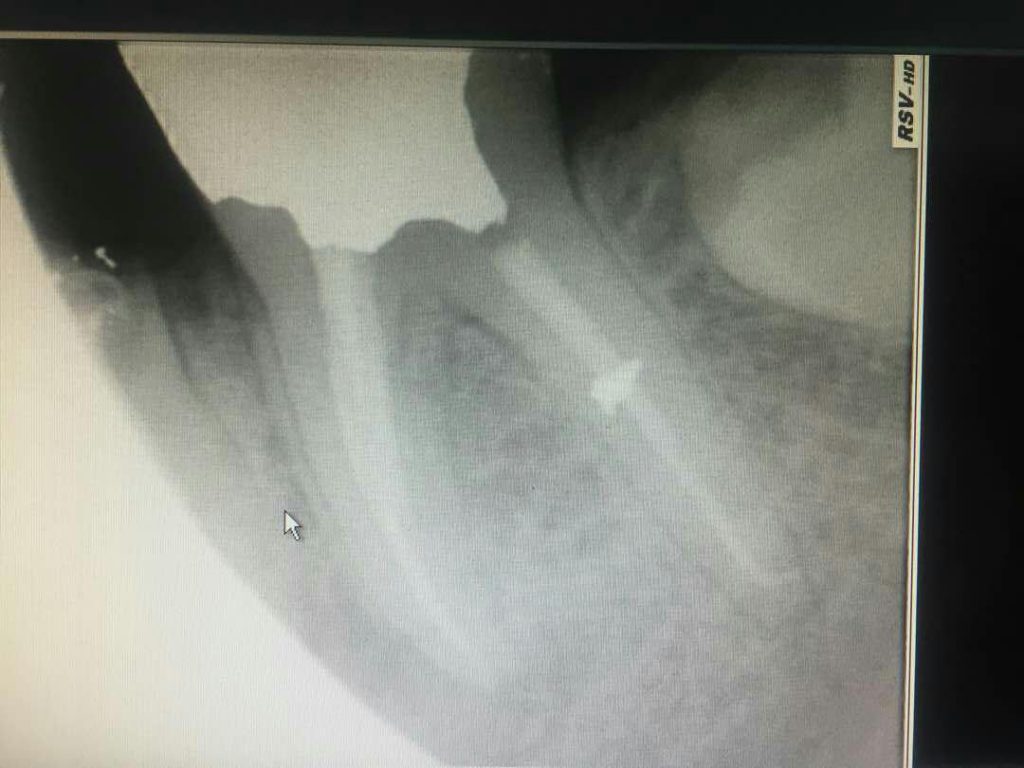

در بعضی موارد مراجعه دیرهنگام فرد برای کاشت دندان (ایمپلنت) یا وجود کیست و تومورهای دهانی منجر به از بین رفتن فضای مناسب و کم شدن قطر و ارتفاع استخوان فک می‌شود که در این حالت، دندانپزشک قبل یا همزمان با جایگذاری فیکسچر، با استفاده از پودر و بلاک استخوانی و ممبرین (بایومتریال‌ها) استخوان را بازسازی کرده تا شرایط مناسب برای قرارگیری ایمپلنت مهیا گردد. در این مواقع طول درمان بیمار (آماده شدن استخوان برای جایگذاری ایمپلنت) بسته به شرایط بیمار از ۳ تا ۶ ماه طول می‌کشد و دندانپزشک به کمک عکس‌های رادیوگرافی می‌تواند روند درمان را دنبال کند و بهترین زمان را برای کاشت ایمپلنت تشخیص دهد.